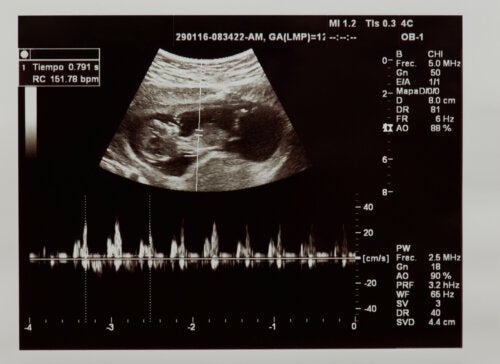

Graviditetens stadier

Kroppen din forandrer seg hver uke, babyen din vokser og så mye mer skjer i kroppen din enn du noen gang forestilte deg. Graviditet er en fantastisk prosess, et mirakel som vi forklare for deg, praktisk og nært, så du kan nyte denne tiden til det fulle.